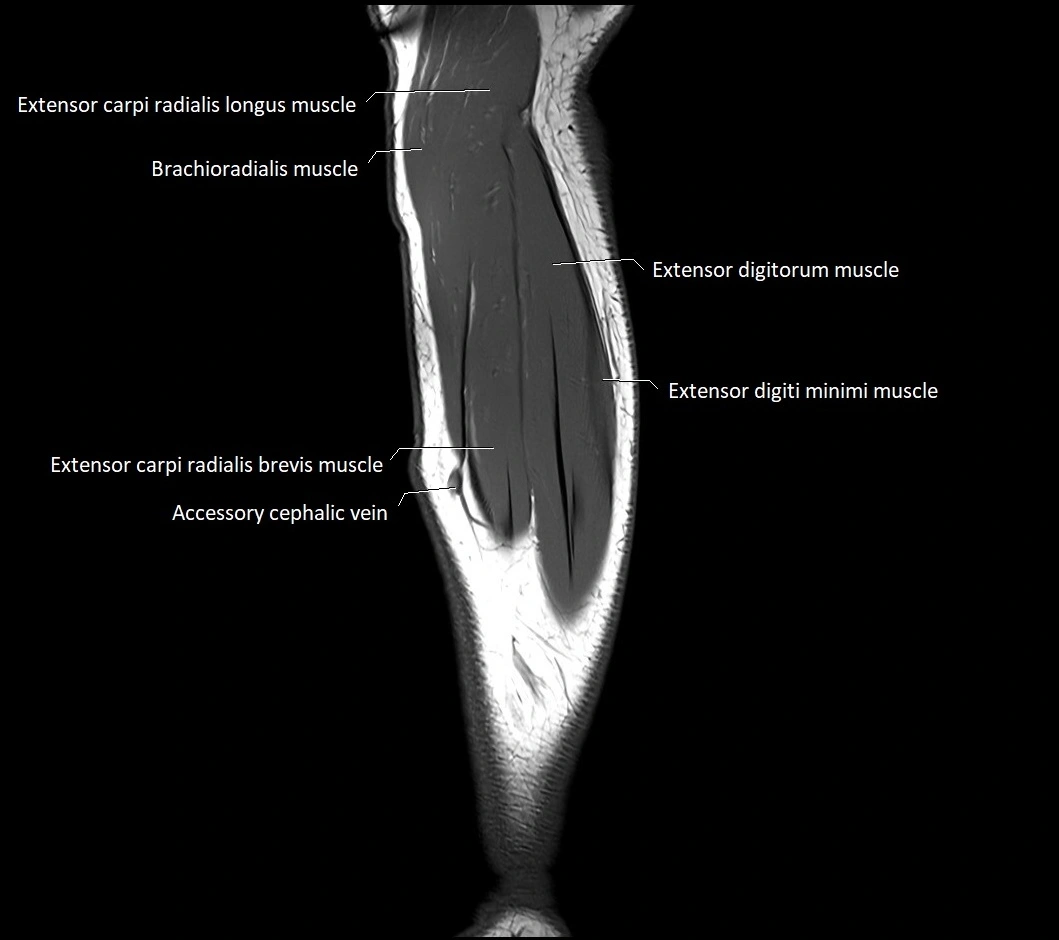

MRI images

image